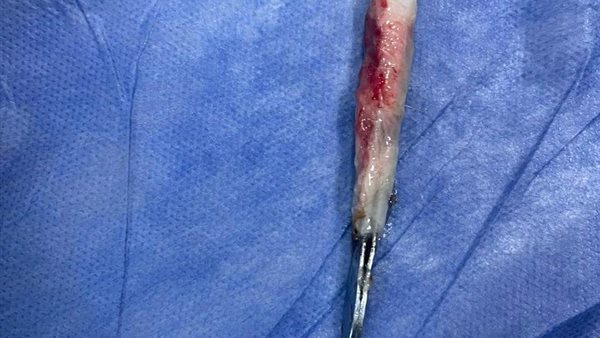

نجح فريق جراحي بقسم جراحة القلب والصدر بمستشفى بنها الجامعى بمحافظة القليوبية، في استخراج ملقاط شعر، من القصبة الهوائية لمريض يعاني من شق حنجري قديم، وأثناء قيامه بتنظيف فتحة الشق الحنجرى بطريقة غير طبية وغير صحيحة باستخدام ملقاط ملفوف بمناديل ورقية، سقط منه وابتلعه ودخل لفتحة القصبة الهوائية.

وأوضح مستشفى بنها الجامعي بمحافظة القليوبية، في بيان له، أنه تم استخراج ملقاط شعر من القصبة الهوائية لمريض يعاني من شق حنجري قديم، وبينما يقوم بتنظيف فتحة الشق الحنجري بطريقة غير طبية وغير صحيحة باستخدام ملقاط ملفوف بمناديل ورقية سقط داخل فتحة القصبة الهوائية.

وتابع المستشفى، أن المريض حضر للقسم في حالة اختناق، وتم دخوله للعمليات فورا، حيث نجح الدكتور باسم مفرح الأستاذ المساعد بالقسم، وبمعاونة الدكتور أحمد الخضري مدرس مساعد التخدير، من استخراج الملقاط، وخرج المريض من العمليات، ويخضع لاستكمال علاجه بالقسم لحين تماثله الكامل للشفاء.